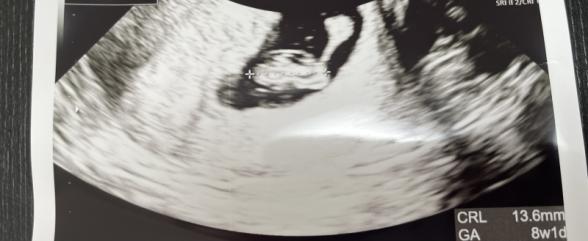

妊娠8週目くらいです。

エコー写真の中で不思議なものが写っているように感じます。

右上の丸から棒のように繋がっていますがこれは何でしょうか。

卵黄嚢だとしたらリング状なのかと思っていました。

何か心配になるようなことがあるのでしょうか。

右上の丸にそこから繋がる棒状のものも、こちらでもよくわからないものでした。

卵黄嚢とはまた違うもののように感じました。

次回の診察の際に、先生へご確認いただけたらと思います。